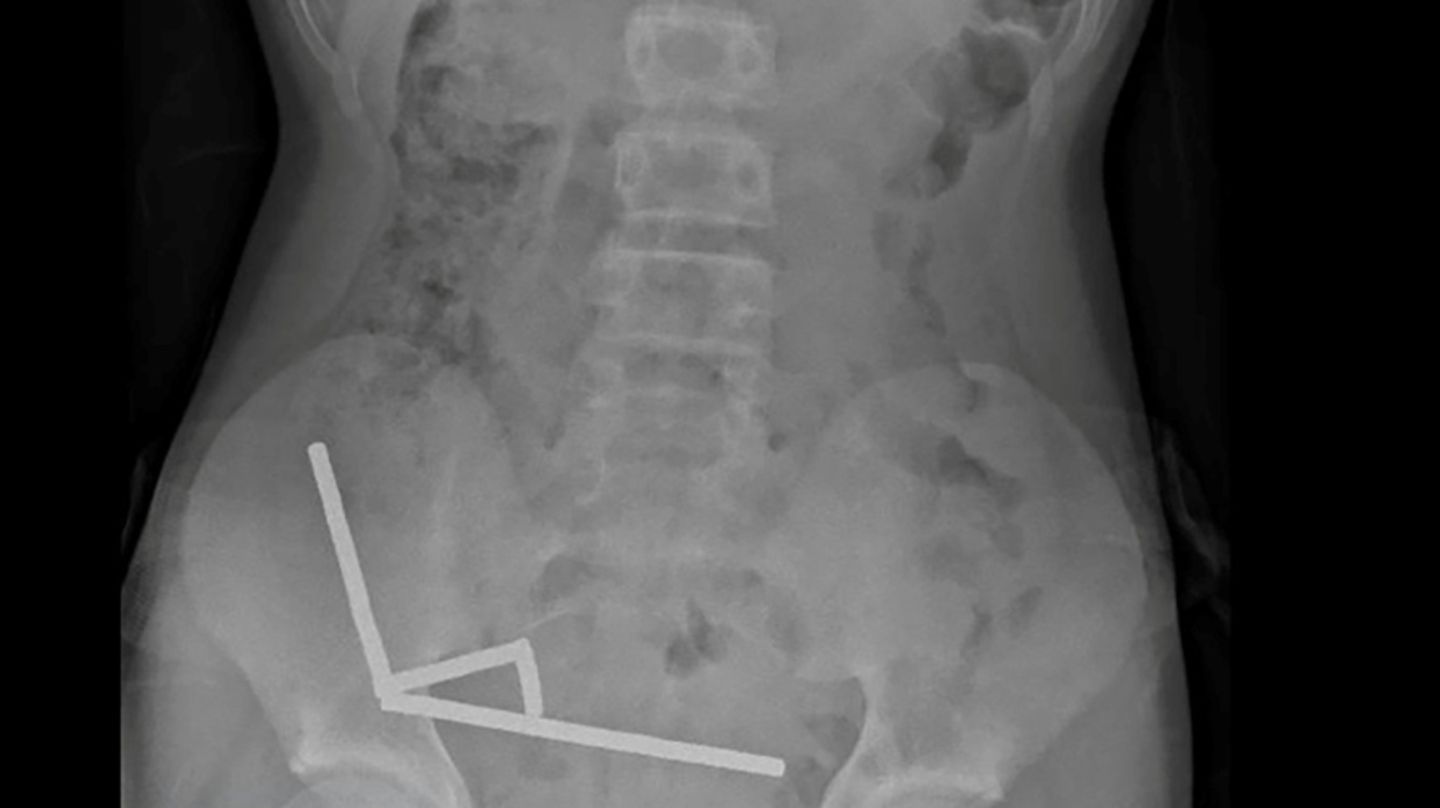

Röntgenbild zeigt die Magneten im Unterleib des 13-Jährigen

Die Magneten, die in Neuseeland seit Anfang 2013 verboten seien, seien auf der Temu-Plattform gekauft worden, teilten die Ärzte mit. Eine Röntgenaufnahme habe gezeigt, dass die Magneten sich in verschiedenen Bereichen des Darms aufgrund der Anziehungskraft zu vier geraden Linien zusammenklumpten. Den Ärzten zufolge starb durch die Kraft der Magneten an vier Stellen im Dünn- und Dickdarm Gewebe ab.